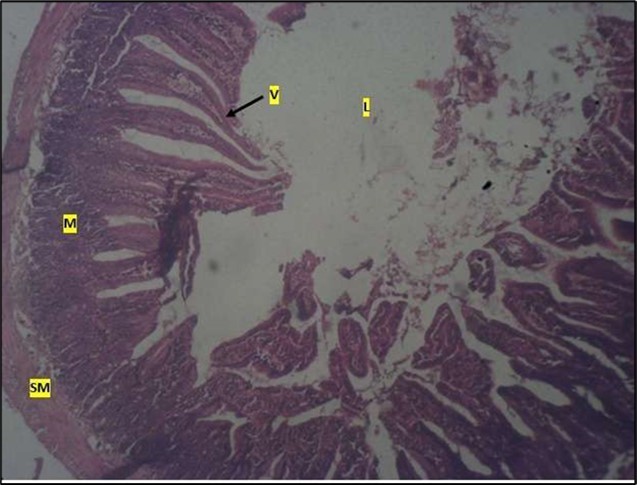

Histological examination of the small intestine result in control animals revealed a normal architecture with the red pulp and white pulp with no pathological observation Figure 2. Administration of Abelmoschus esculentus at low dose shows an increased cellularity with numerous cells in the Mucosa and the villi projecting towards the lumen. Focal metaplasia of mucosal cells alongside villous disruption was also observed (Figure 3). The high dose group showed normal cellular architecture with no villous disruption (Figure 4).

Figure 4.High dose showing a normal mucosa (m) with villi (v) projecting towards the lumen(l) and underlying smooth muscle layer (sm). No pathology seen

High dose showing a normal mucosa (m) with villi (v)                 projecting towards the lumen(l) and underlying smooth muscle layer (sm). No pathology seen